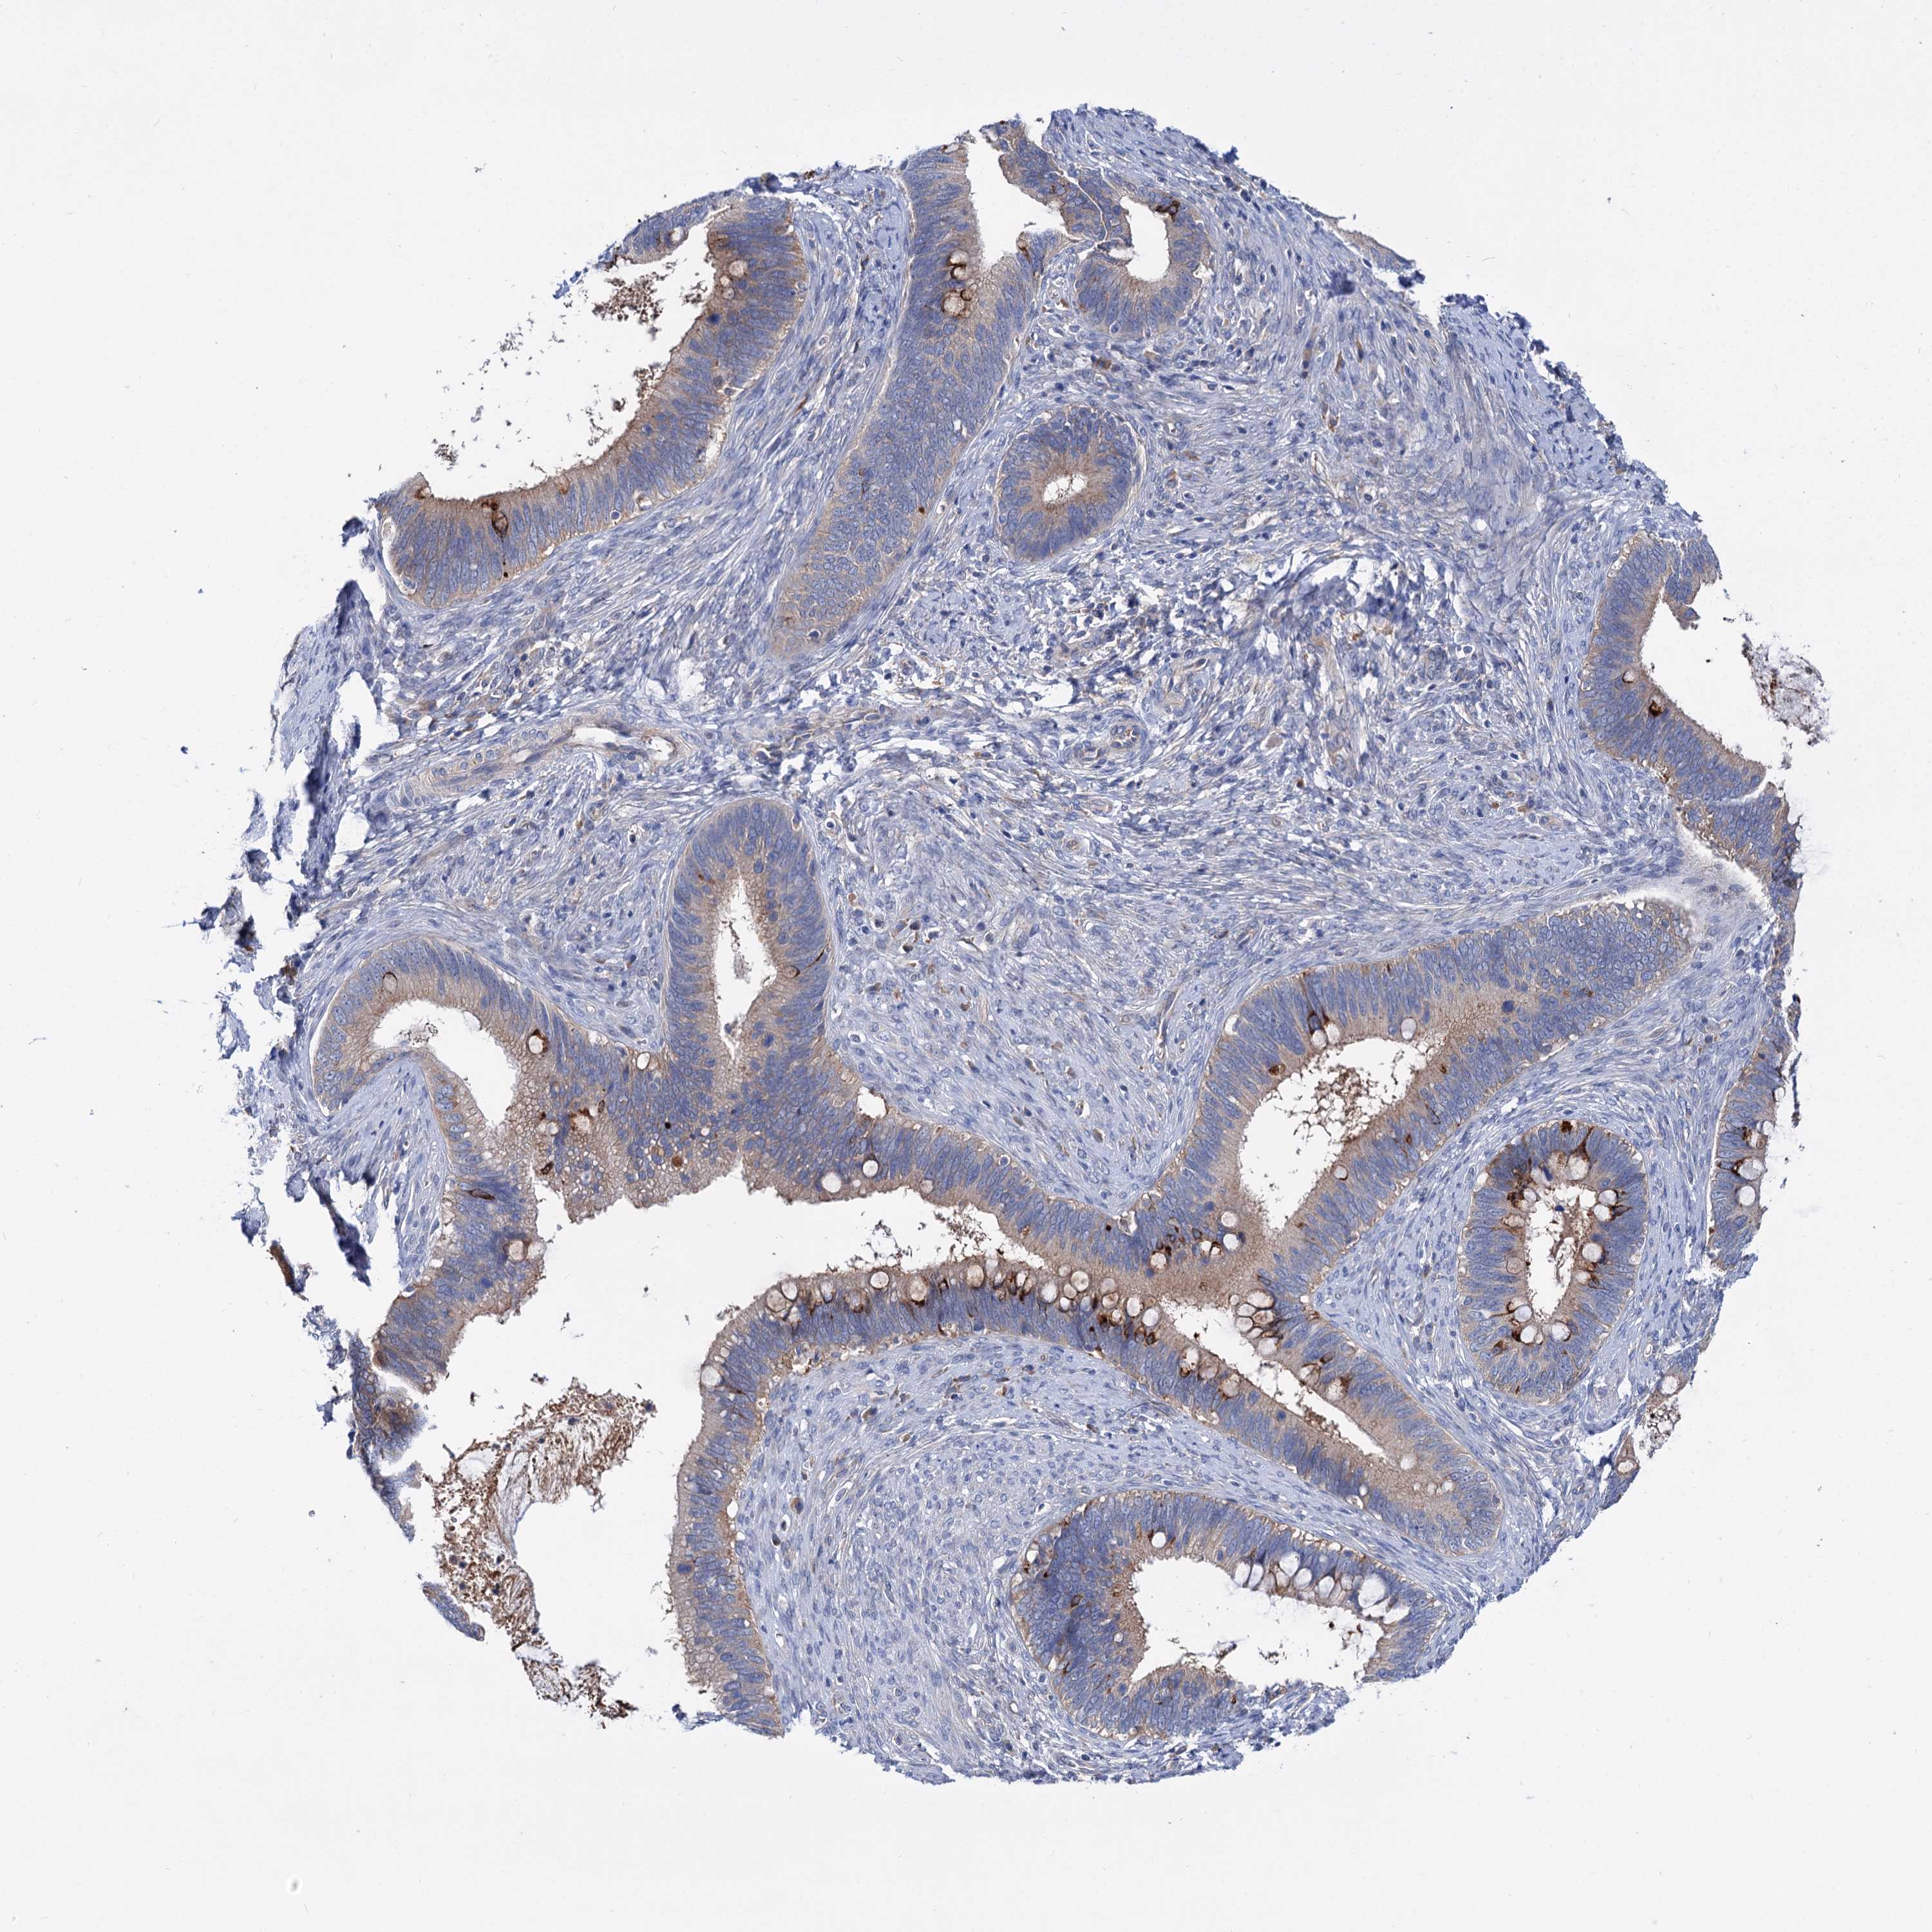

CERVICAL CANCER - Protein expressioni

A mouse-over function shows sample information and annotation data. Click on an image to view it in a full screen mode. Samples can be filtered based on level of antibody staining by selecting one or several of the following categories: high, medium, low and not detected. The assay and annotation is described here.

Note that samples used for immunohistochemistry by the Human Protein Atlas do not correspond to samples in the TCGA dataset.

Antibody stainingi

Antibody staining in the annotated cell types in the current human tissue is reported as not detected, low, medium, or high, based on conventional immunohistochemistry profiling in selected tissues. This score is based on the combination of the staining intensity and fraction of stained cells.

Each image is clickable and will lead to virtual microscopy that enables deeper exploration of all samples and also displays staining intensity scores, fraction scores and subcellular localization as well as patient and tissue information for each sample.

Antibody HPA038793

Antibody HPA053691

Staining

High

Medium

Low

Not detected

Intensity

Strong

Moderate

Weak

Negative

Quantity

>75%

75%-25%

<25%

None

Location

Nuclear

Cytoplasmic/membranous

Cytoplasmic/membranous,nuclear

Squamous cell carcinoma, NOS

Adenocarcinoma, NOS